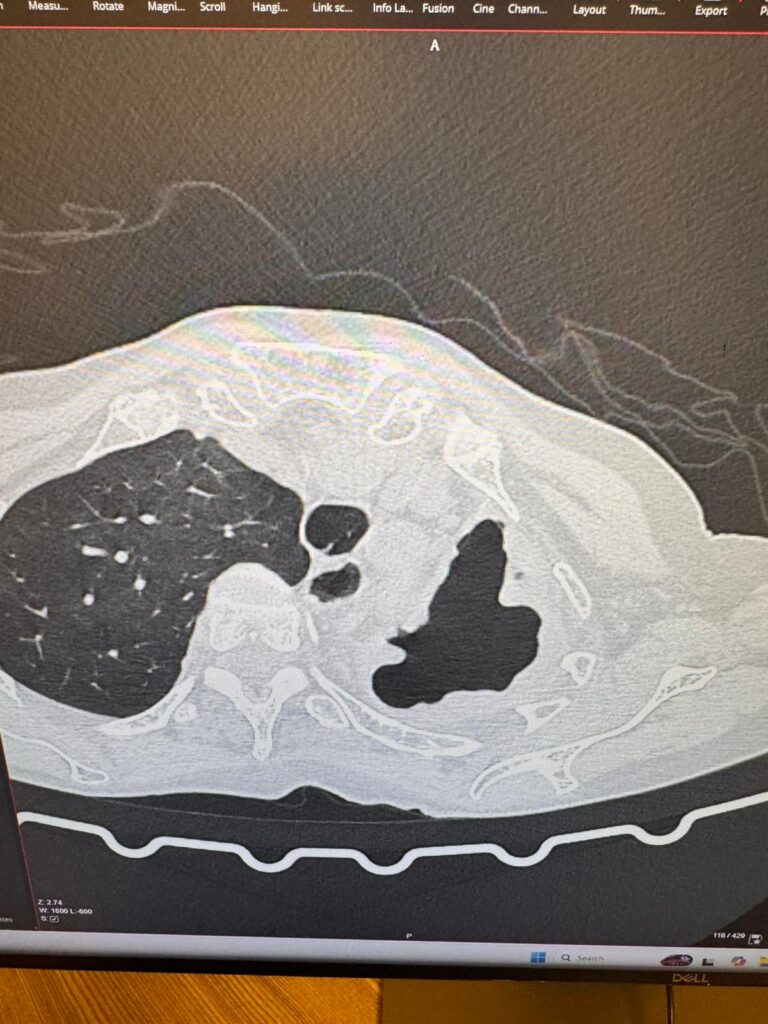

La misión en Liberia incluyó tres neumonectomías por pulmones destruidos, una lobectomía por aspergiloma, y tres intervenciones adicionales. Todas realizadas mediante la técnica Uniportal VATS en la única unidad quirúrgica móvil del mundo capaz de practicar este tipo de cirugía.